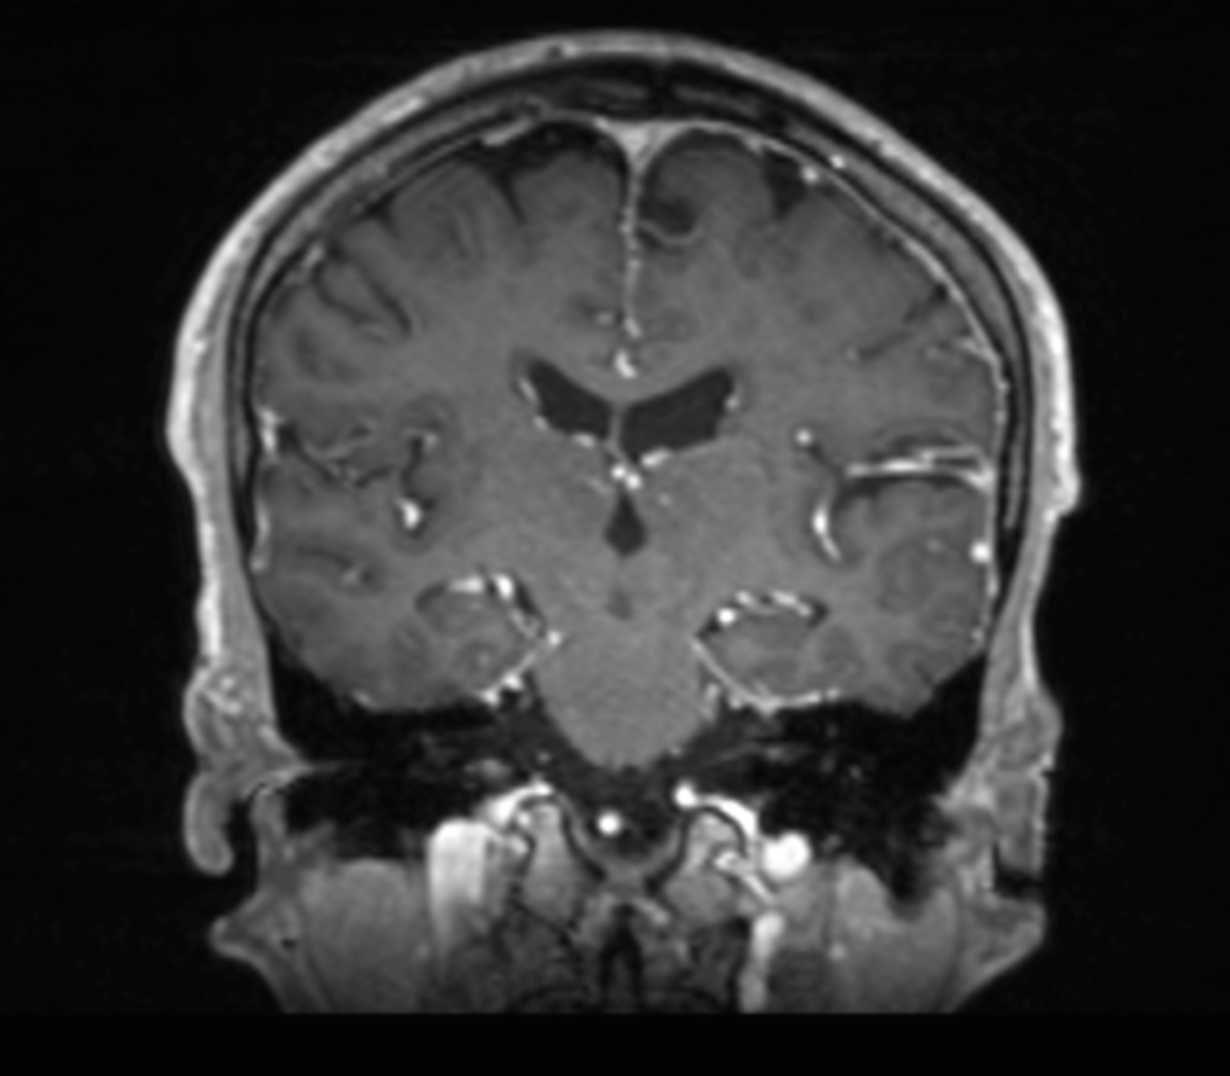

Quelle est la séquence de cet IRM ?

T1 Gado - coupe frontale